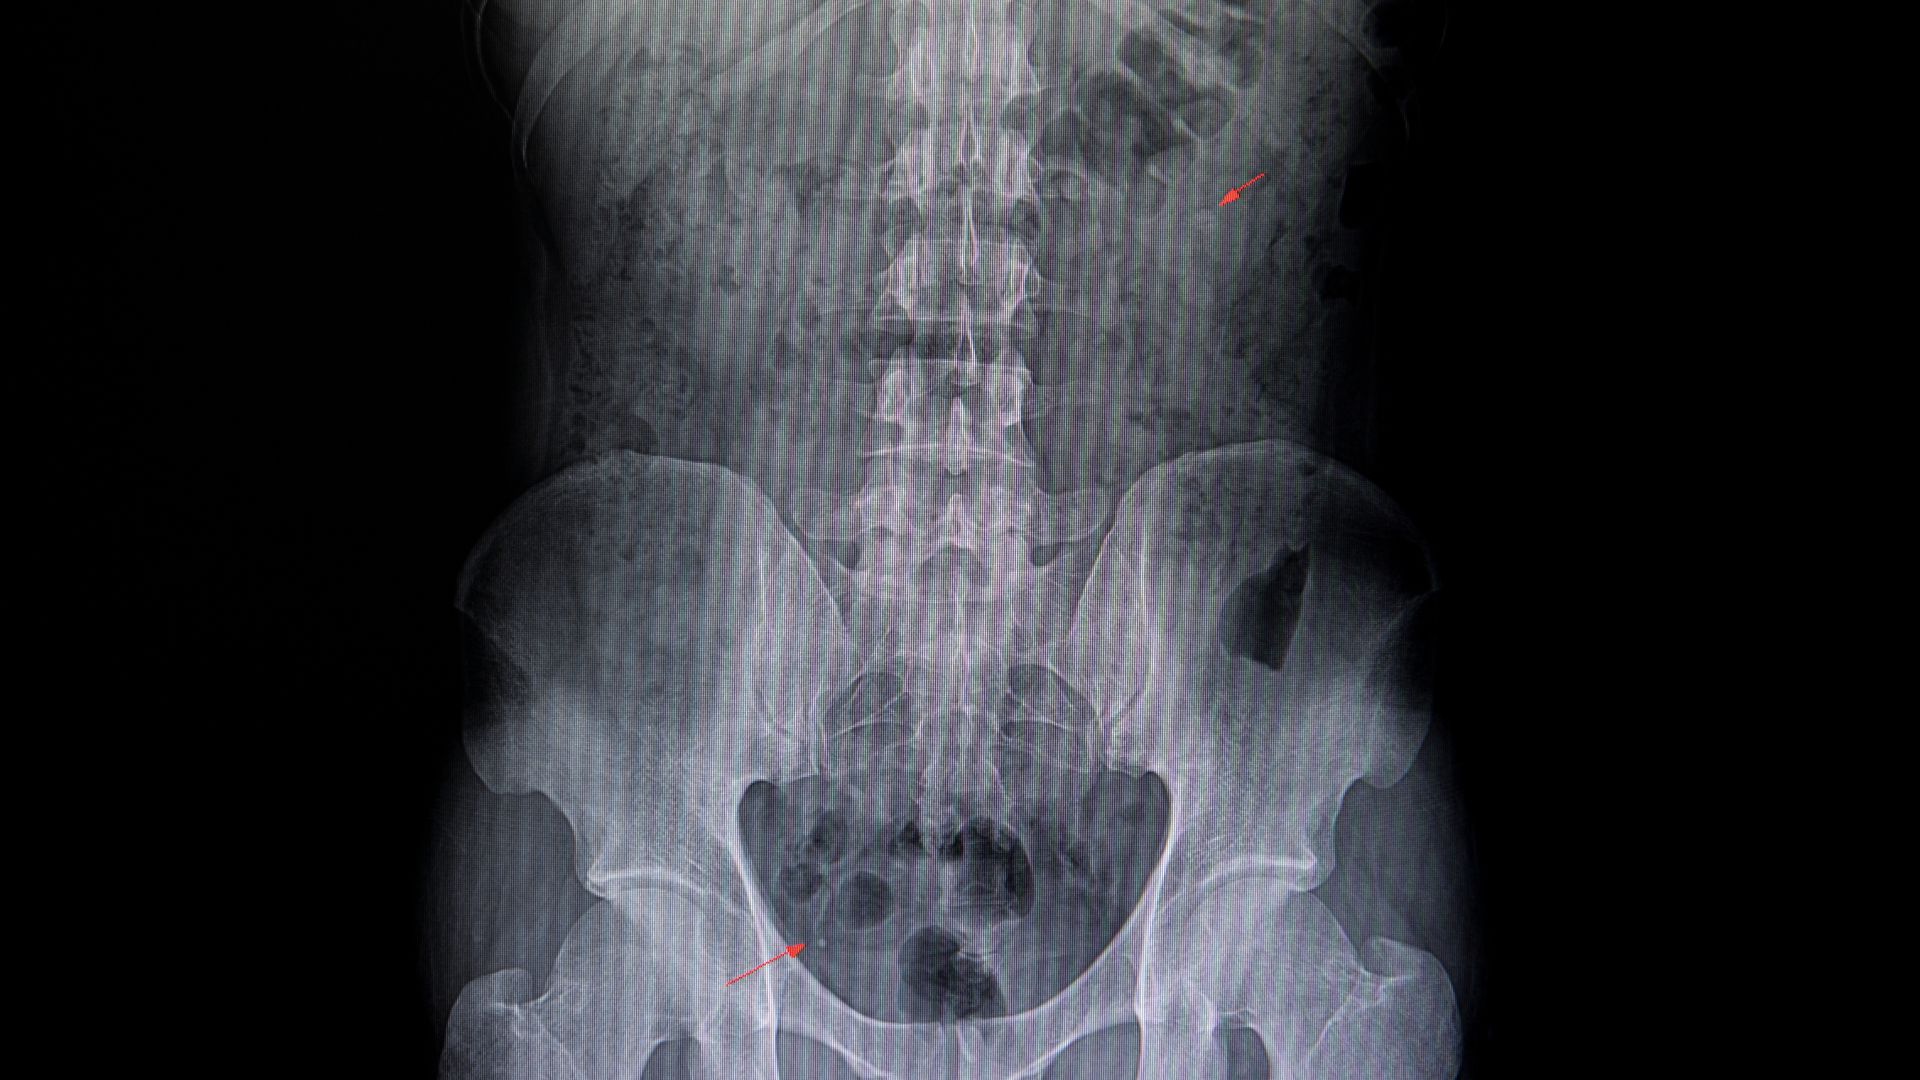

- Phương pháp chẩn đoán: Bác sĩ có thể chỉ định siêu âm, CT scan hoặc chụp X-quang hệ tiết niệu để đánh giá tình trạng niệu quản một cách chính xác.